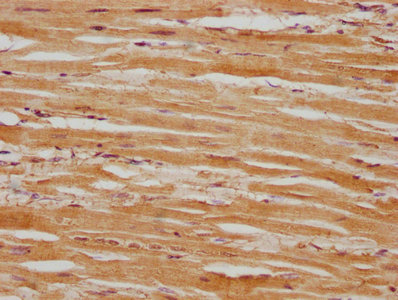

• IHC image of CSB-PA618751LA01HU diluted at 1:100 and staining in paraffin-embedded human heart tissue performed on a Leica BondTM system. After dewaxing and hydration, antigen retrieval was mediated by high pressure in a citrate buffer (pH 6.0). Section was blocked with 10% normal goat serum 30min at RT. Then primary antibody (1% BSA) was incubated at 4°C overnight. The primary is detected by a biotinylated secondary antibody and visualized using an HRP conjugated SP system.